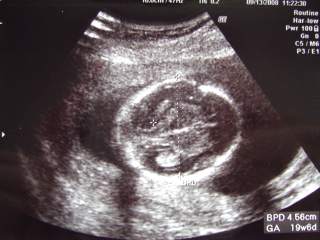

19週目に突入しました♪今日は1ヶ月ぶりに実家に帰って、里帰り出産予定の産院に行ってきました本当は、34週になるまで行かなくて良いのだけど、土曜日もやってくれている産院なので、相棒と一緒に赤ちゃんの成長をエコーで見られるのです!エコーによる対面を楽しみにしている相棒が、「今度はいつ?今度はいつ?」と急かすので3連休の初日に合わせて行くことにしました♪30分程待って診察室に入ると、院長先生はお休みで代務の先生が待っていました電話予約をした時に聞いていた事だったので、少しお話をしてから相棒お楽しみのエコータイムとなりました♪「これが頭ですねぇ~」「これがお腹ですねぇ~この黒い所は胃袋ですねぇ~」と、頭からだんだん下に向かって赤ちゃんを輪切りにしていきます♪お尻~足が写った所で、股の辺りに何やらうつっています・・・心の中で「あ!」っと思った相棒と私・・・先生は何事もなかったかのように通り過ぎて、何も見なかったかのように聞きました・・・「そういえば、性別とかもう聞いてますか?」と先生。「いえ、まだ聞いていません」と私。「聞かない方が良いですかねぇ?」と相棒の顔を見ながら尋ねる先生・・・・・・って、先生、今みえてたじゃん!?「でも、今何か写ってましたよねぇ?」と私が言うと「あははは~写ってましたねぇ・・・秘密・・・っていう訳にもいかないですかねぇ?」とあたふたし始める先生・・・前回アンケートの時に、あかちゃんの性別とか病気とか事前に分かる範囲で知りたいかどうかというアンケートを書いていたのですが、(その時は、全部教えて欲しいに○を打ちました♪)中には生まれるまで、何も知りたくないという親御さんもいらっしゃるのでこの夫婦はどっちだったかなぁ?って先生が思われたのかもしれません・・・「男の子ですよね?」と再度念押しすると、「男の子ですよ~」と、観念(?)したかのように、教えてくれました♪実は前々から男の子という事はある事情で分かっていたので、別に驚きませんでしたが、やっぱりそうか~という喜びはありました♪(その内、ブログに書く機会があれば・・・お話しますね♪)それからは、何だかしつこくお股の部分をエコーで映してくれるので苦笑しながらも、楽しくエコーを見させて頂きましたちょっと前置胎盤の気があるとの事だったので、内診によるエコーも取りましたが子宮孔から現時点で7mmずれているということで、まぁ大丈夫でしょうとお話を受けました健診に行っている病院でも、前回の院長先生の診察でも、前置胎盤とは言われてなかったので、別に心配していませんでしたが、まぁ、時々は健診の病院でも検査してもらおうかなって思いました♪顔アップ♪左側が上で、顔の中心くらいのくぼんだ所が眼窩です♪お尻から足です♪この日の赤ちゃんは、足を伸ばして前屈姿勢していたみたい・・・苦しくないのかなぁ?動画では、手で足を触っているような場面も見られました♪(残念ながら、この写真では例のモノは隠れてしまってます・・・笑)3D(4D?)写真です♪頭が上で顔がやや右向きです手と足で隠れていますが、何となく鼻と口元が見えるかなぁ?という感じです♪